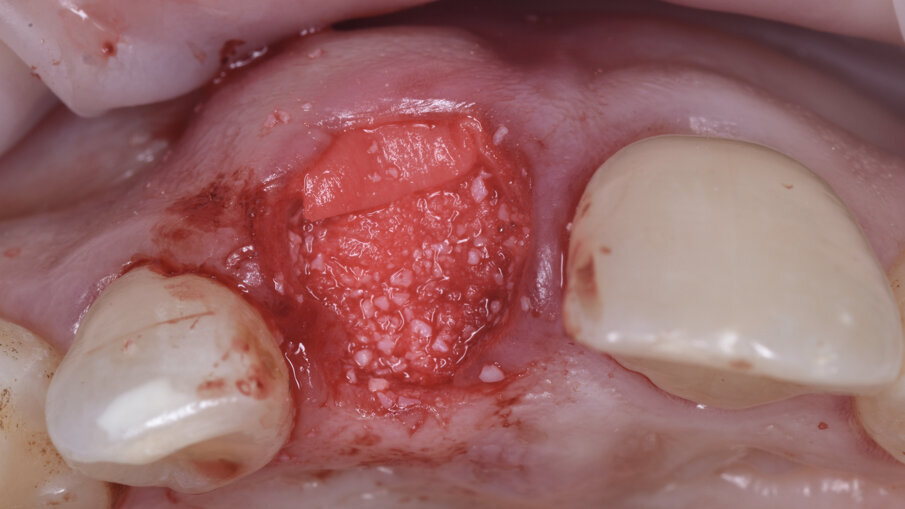

È stata quindi eseguita un’incisione vestibolare intrasulculare del sito senza toccare le papille, facendo scorrere la lama sul piano osseo crestale, e nella porzione più apicale dove era presente la discontinuità della corticale si è spostato la lama mesiale e distale e ancora apicale fino a ritrovare il piano osseo secondo le indicazioni della CBCT; è stato possibile così inserire una membrana in collagene suina Geistlich Bio-Gide (Geistlich Pharma AG, Wolhusen, Switzerland) opportunamente sagomata in modo che avesse un appoggio sui piani ossei (Fig. 4); all’interno dell’alveolo è stato posizionato Geistlich Bio-Oss Collagen (Geistlich Pharma AG, Wolhusen, Switzerland), osso bovino deproteinizzato con un 10% di collagene suino addizionale, materiale osteoconduttivo che oltre a essere mantenitore di spazio e scaffold per la rigenerazione ossea, funge anche da sostegno per il tessuto molle soprastante (Fig. 5). Si è quindi proceduto dopo anestesia palatale a un prelievo tramite bisturi circolare di un punch epitelio connettivale di forma tondeggiante e misure simili all’alveolo dell’1.1 da sigillare; dopo la disepitelizzazione dei margini dell’alveolo si è proceduto alla sutura del punch al di sopra del sostituto osseo con suture Vicril 6-0 (Johnson & Johnson Medical Spa, Pomezia RM, Italia) con punti staccati alle quattro estremità e sutura a materassaio esterno incrociato compressiva (Fig. 6). In questa fase la paziente è stata riabilitata con un maryland bridge in composito cementato adesivamente.